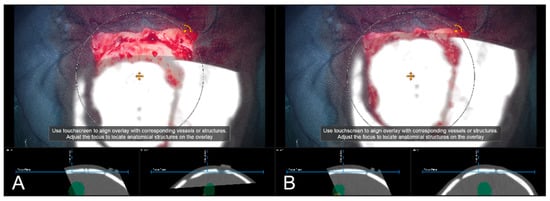

Alternative to bony and/or vascular landmarks, in 40 cases (13.65%) a cortex representation gained by automatic segmentation of cranial structures was used to evaluate and verify navigational accuracy. As the in-plane object representation is not straightforward, the Overview View was used firsthand in all cases to evaluate navigation accuracy allowing for superimposing the microscope video on the 3D visualization of the segmented data, see Figure 9. If a mismatch was seen, switching to the navigation update feature allowed for an in-plane transformation of the date to overcome the seen misalignment in the focus plane. This was the case in two patients (5.00%), whereas in the remaining 38 cases (95.00%), there was no need for further alignments was seen. In both cases, a linear transformation by on average 5.31 ± 1.57 mm and 1.75° ± 2.47° led to sufficient accuracy.

Figure 9.

Superimposing the microscope video on the 3D visualization of patient MRI data including the pre-segmented objects (cerebrum and tumor) intuitively relating video frame and 3D anatomy (upper part in A–D), in parallel view of AR-supported microscope view, probe’s eye view and target view (bottom part in A–D from left to right). Moving the focus plane (superimposed microscope video) along the optical axis of the microscope (A–D), the registration quality can be evaluated showing a sufficient match in this case.